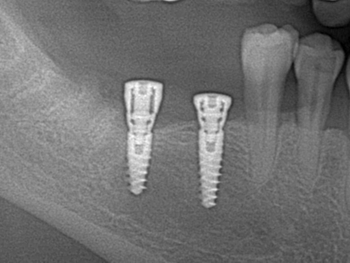

13a. 13b. Postoperative radiographic evaluation of both quadrants operated on.